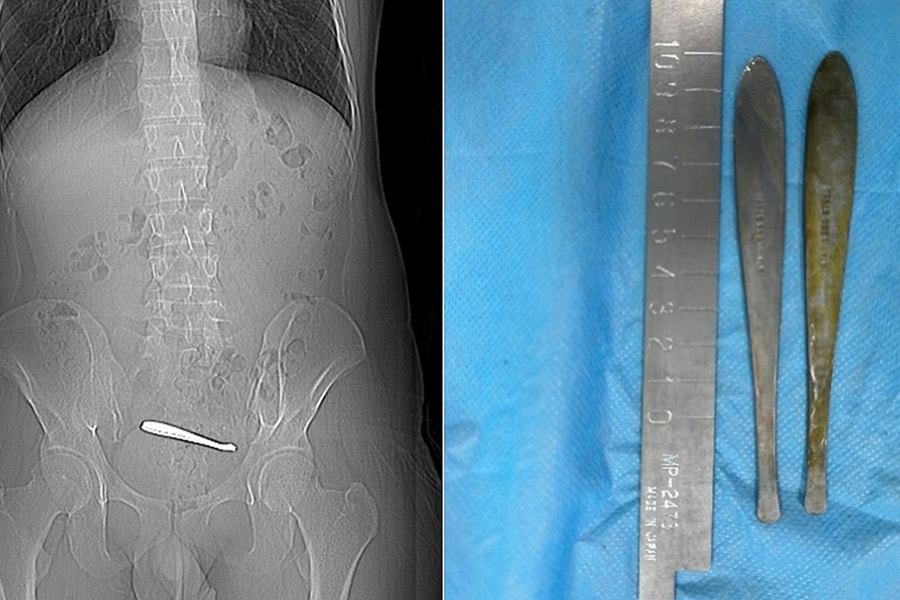

2 chiếc thìa 12 cm kẹt trong ruột chàng trai

Vô tình nuốt phải chiếc thìa, nam thanh niên 28 tuổi nhập viện vì đau bụng dữ dội, trước khi được các bác sĩ nội soi gắp thành công hai dị vật dài 12 cm.